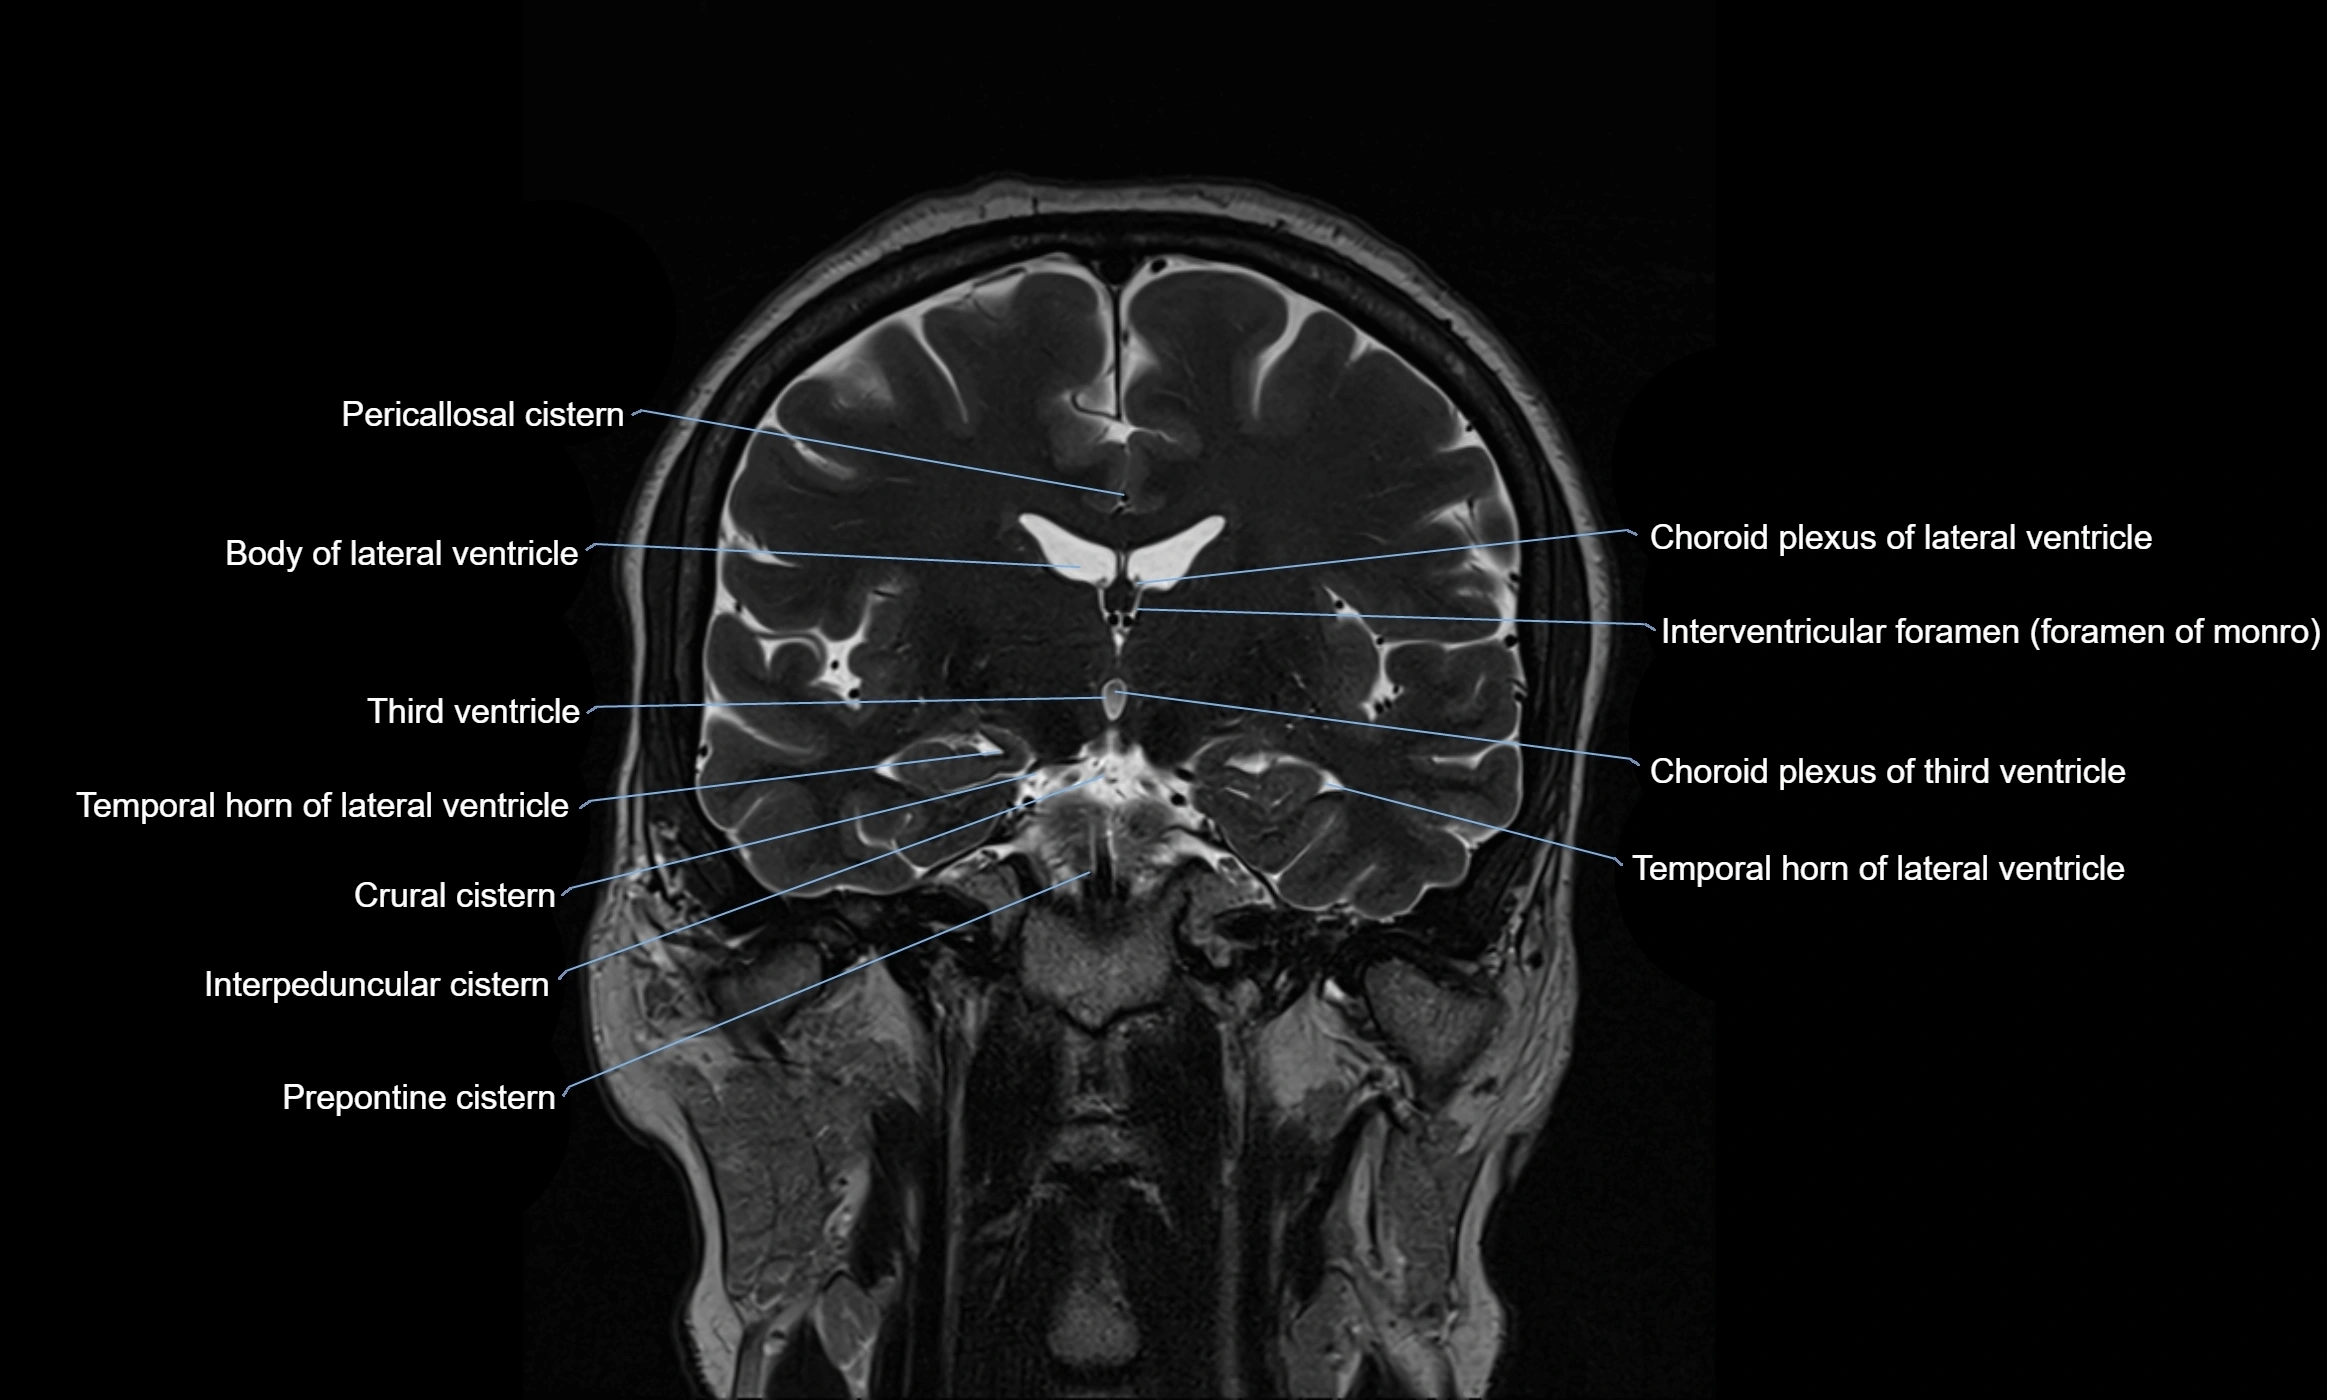

Ambient cistern

The ambient cistern is a paired, narrow, and elongated subarachnoid space located bilaterally along the lateral aspect of the midbrain. It serves as a conduit between the interpeduncular cistern anteriorly and the quadrigeminal cistern posteriorly. This cistern houses critical neurovascular structures, including parts of the posterior cerebral artery, superior cerebellar artery, trochlear nerve (cranial nerve IV), and the basal vein of Rosenthal. It plays an important role in the circulation of cerebrospinal fluid (CSF) and provides an anatomical corridor for various vessels and nerves passing around the midbrain.

• Contains and cushions neurovascular structures adjacent to the lateral midbrain

• Acts as a pathway for CSF flow between the interpeduncular and quadrigeminal cisterns

• Provides a corridor for the passage of arteries, veins, and the trochlear nerve